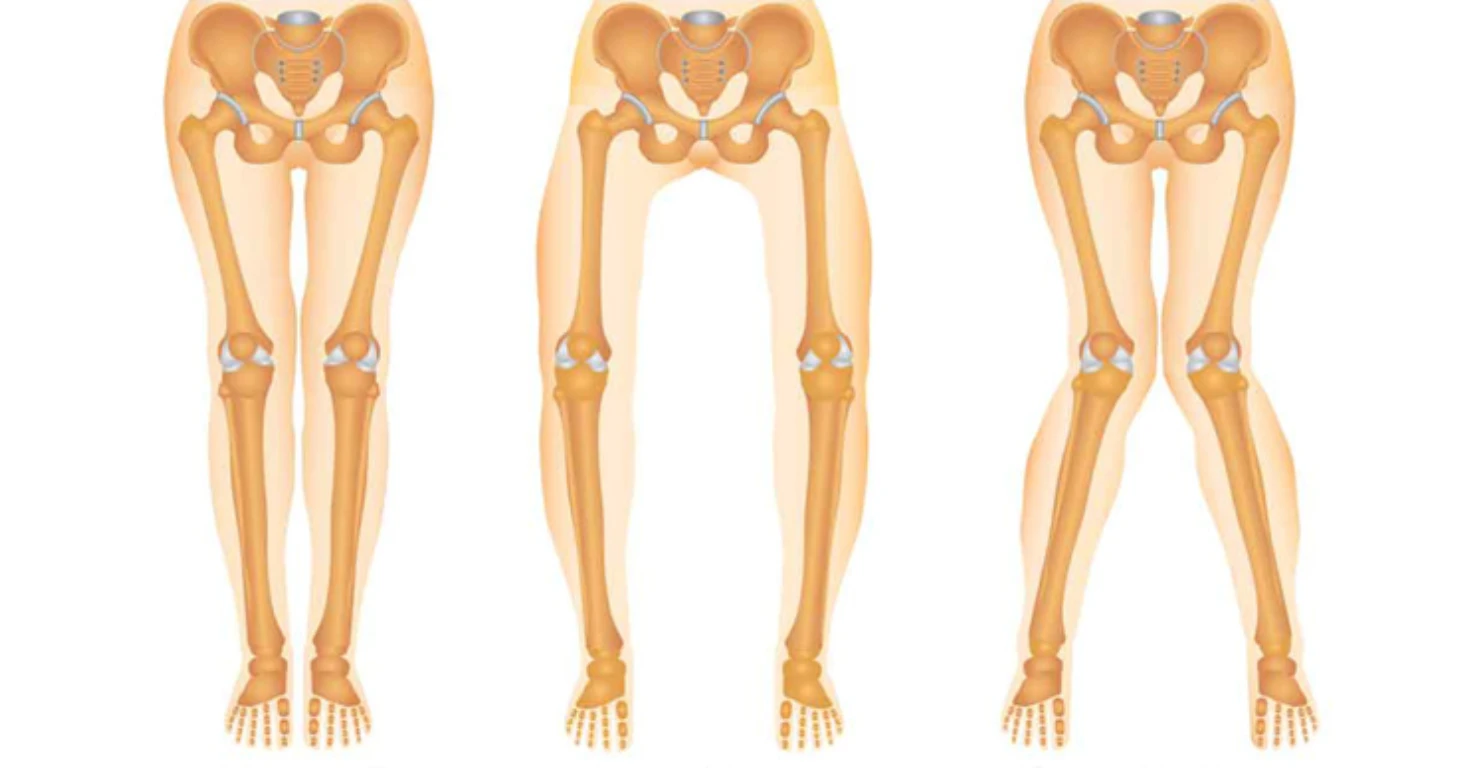

پای پرانتزی یک ناهنجاری در راستای طبیعی استخوانهای پا و زانو است که باعث میشود زمانی که مچ پاها کنار یکدیگر قرار میگیرند، زانوها به هم نرسند و بین آنها فاصله ایجاد شود. در حالت طبیعی، محور ران، زانو و مچ پا باید روی یک خط مستقیم قرار بگیرند؛ اما در فردی که پای پرانتزی دارد، این محور به سمت بیرون منحرف میشود و نتیجه آن تغییر در شیوه راه رفتن و ایستادن بدن است.

این ناهنجاری تنها یک مسئله ظاهری نیست، بلکه بهطور مستقیم روی عملکرد مفاصل و سلامت حرکتی بدن اثر میگذارد. زمانی که محور پا از حالت طبیعی خارج میشود، وزن بدن به جای آنکه بهطور یکنواخت در کف پا پخش شود، بیشتر روی لبهی خارجی پا و مفصل زانو متمرکز میگردد. این توزیع غیرطبیعی فشار، در طول زمان منجر به بروز مشکلات متعددی میشود؛ از جمله:

- افزایش فشار بر مفصل زانو و احتمال ساییدگی زودرس غضروف

- درد در ناحیه لگن به دلیل تغییر تراز حرکتی بدن

- فشار انتقالی به ستون فقرات و کمردرد مزمن